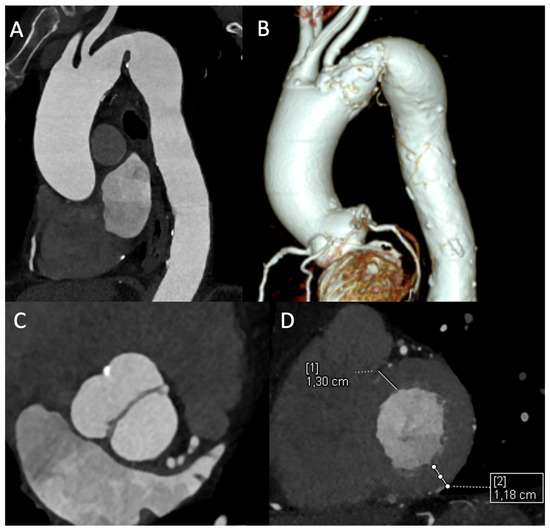

Cardiovascular magnetic resonance (CMR) imaging has emerged as a cornerstone in the non-invasive assessment of cardiac structure, function, and tissue characterization. With its unparalleled spatial resolution, reproducibility, and versatility, CMR enables accurate diagnosis across a wide spectrum of cardiovascular diseases, including cardiomyopathies, ischemic heart disease, myocarditis, valvular disorders (particularly mitral valve prolapse), and congenital anomalies. Beyond diagnosis, CMR is increasingly recognized for its pivotal role in guiding therapeutic decisions—ranging from risk stratification and timing of interventions to monitoring treatment response.

The evolution of advanced techniques such as T1 and T2 mapping, late gadolinium enhancement, strain imaging, and 4D flow has expanded the clinical utility of CMR beyond traditional volumetric and functional assessment. These innovations not only improve diagnostic precision but also enhance our ability to personalize therapy and predict outcomes.